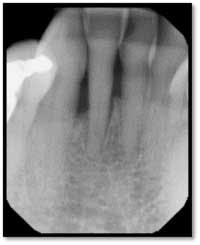

A full set of radiographs taken 13 months post therapy show bone fill in the deepest pockets, with generalized pocket reductions of up to 7mm.

#3 was referred for endodontic evaluation.

#’s 15 and 18 show no signs of endodontic involvement, #15 tests vital.

This patient now has a periodontally stable dentition for the first time in his adult life and is very happy with the outcome of his therapy.